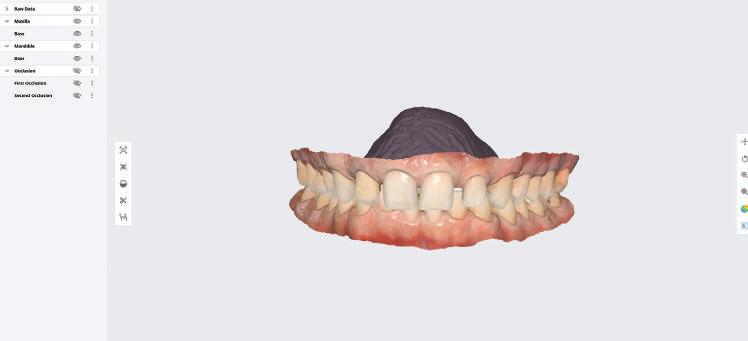

След диагностиката бяха направени екстра- и интраорални снимки, както и рентгенографии; професионалното почистване бе от изключителна важ ност, бяха дадени и инструкции за лич на орална хигиена. Бе направено интра орално сканиране с Medit i500. Цялата тази информация бе използ вана в приложението Smilecloud за 2D биометричен дизайн. В приложението са налични естест вени форми на зъбите и щом бяха под брани зъби и бе направен дизайн

библиотеката на Exocad. Струва си да се отбележи, че 2D дизайнът от Smile Cloud бе спазен до последния детайл в Exocad smile creator с цел да се създаде 3D obj файл със зъбните форми. След като естетичният дизайн бе готов в model creator модула на Exocad, адитивен 3D мок-ъп модел бе експорти ран и принтиран от принтер Formlabs 3. Моделът бе използван за направата на силиконов водач, за да се изготви мо тивационен мок-ъп в устата на паци ента и да се оценят естетичните па раметри. След като пациентът одобри вида на усмивката си, мок-ъпът бе използван за финализиране дизайна на усмивка та. Мок-ъпът бе използван също така като водач по време на мекотъканна та хирургия, както и при препарация на зъбите.

Препарираните зъби бяха импорти рани в Exocad и насложени върху ес тествените форми от биометричния дизайн, като така стана ясно дали зъ бите са били препарирани коректно. По този начин зъболекарят и зъботехни кът работят в една и съща екосистема и резултатът е оптимален. С короната се справихме чрез диги тална редукция на циркония в Exocad, като по този начин на практика създа дохме циркониево кепе, след което про изведохме фасета от IPS Empress Cad Multi. Кепето от Katana Zirconia на зъб 12 с букално послойно нанесена керами ка бе фрезовано (послойното нанасяне бе направено, за да се подобри връзката и да се осигури адхезивно циментиране на фасетата към циркониевото кепе, както и за да се напасне цветът към този на съседните зъби). При първото сканиране регистрирах ме цялата горна зъбна дъга, така че, ко гато се наложи да сканираме повторно, бе изтрит и сканиран наново само зъб 12, тъй като венците не бяха отдръп нати при второто сканиране.

рентгенографии. Инициална терапия и професионално почистване. Интраорално сканиране с цел диги тално планиране. Регистрация и 3D ориентиране на ок лузалната равнина на горна и долна челюст в пространството. 2D дигитално планиране и дизайн на усмивката посредством приложение то Smile Cloud. 3D дигитално планиране и дизайн на функционалните и естетичните па раметри. 3D дигитален дизайн и адитивен мокъп на горна челюст. 3D принтиране и мок-ъп модели. Мотивационен мок-ъп. Фини корекции за постигане на фи налния дизайн. Мекотъканна хирургия с мок-ъпа като водач Препарация през мок-ъпа, използвай ки дизайна като водач за финалната препарация в Exocad. Циркониево кепе ще бъде циментира но с цел адхезивно залепяне на фасе та на края. Кепето има същия цвят като този на съседните зъби, за да може фасетата да се впише перфект но в цялостната усмивка. Изработване на 12 IPS Empress Cad Multi фасети с послойно нанесена ке ТОТАЛНА РЕХАБИЛИТАЦИЯ НА УСМИВКАТА С ИЗЦЯЛО ДИГИТАЛЕН ПРОТОКОЛ Д-р Калин Маринов и зт. Стефан Петров рамика букално върху зъбните препа рации и върху първичното циркони ево кепе (има възможност за ецване и адхезивно